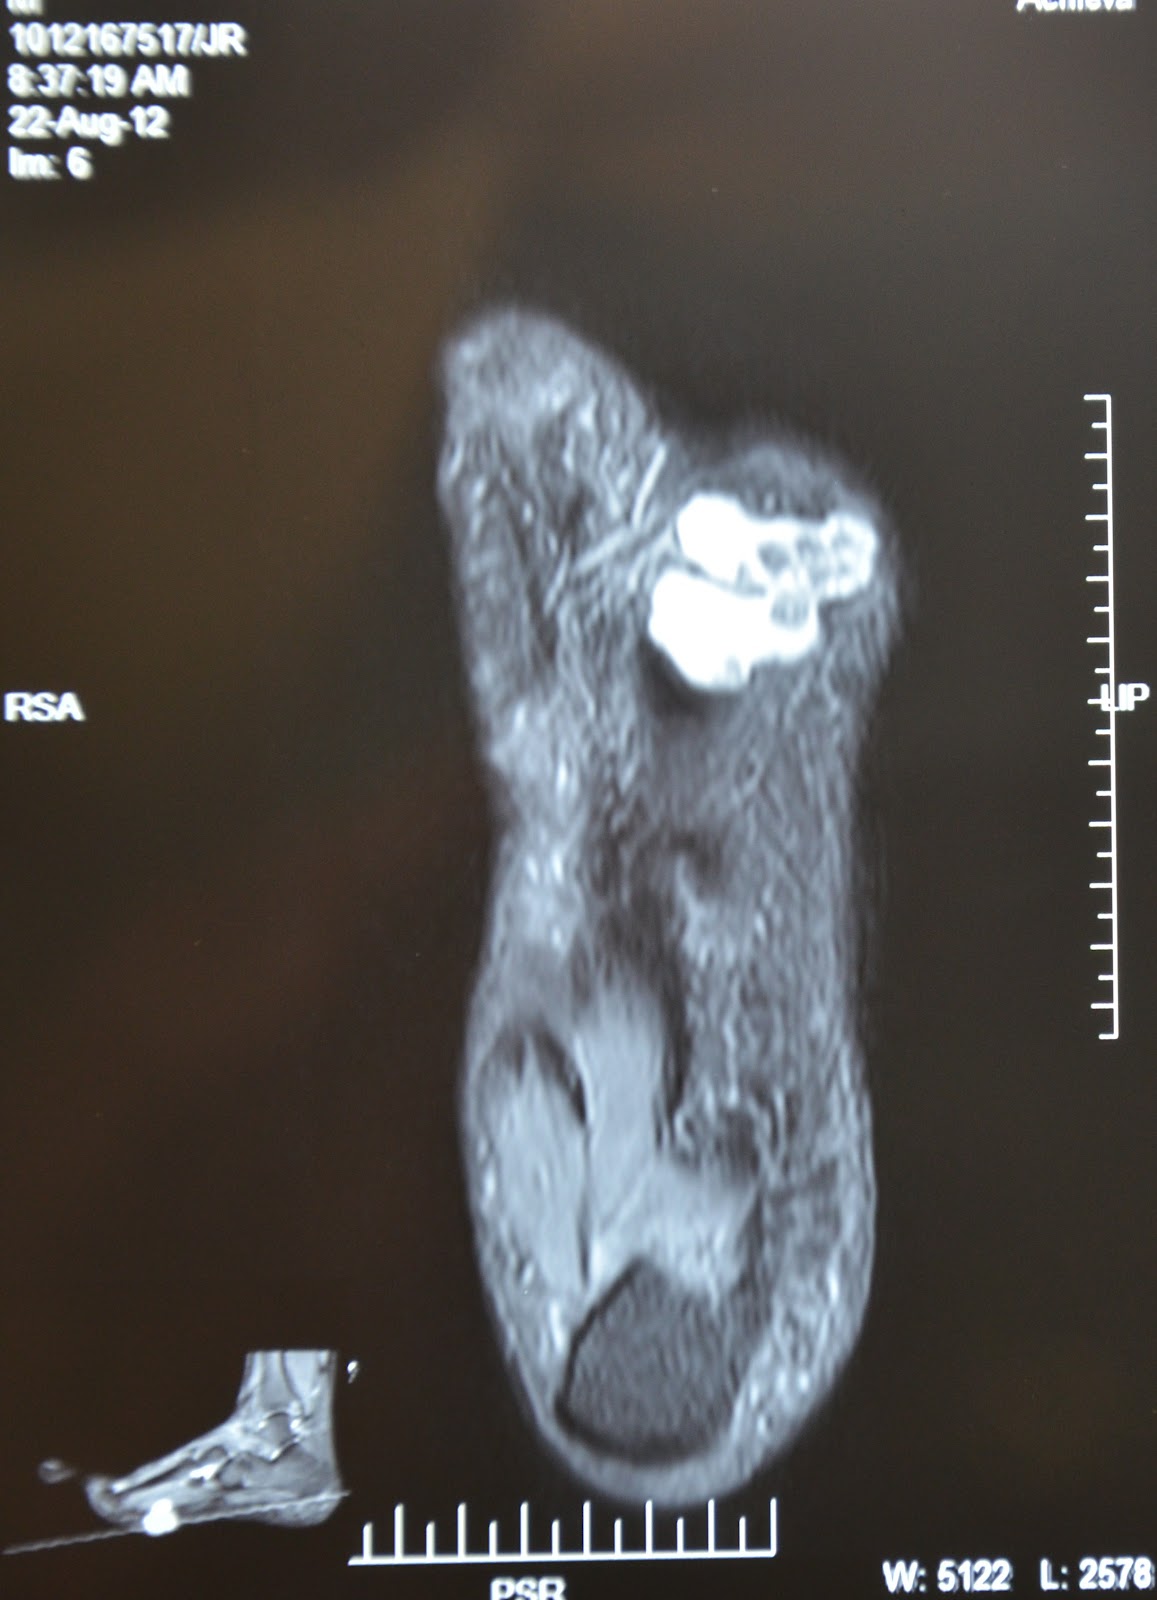

Cureus Heavily Ossified Soft Tissue Chondroma of Plantar Foot and the Plantar Foot Tumors — the majority of soft tissue lesions in the foot and ankle are benign. The aim of this review is to provide the reader. plantar fibromas are nodular masses arising in the plantar aponeurosis of the foot. This nodule is embedded in the plantar fascia. It affects the plantar fascia, which is the thick layer of. this. Plantar Foot Tumors.